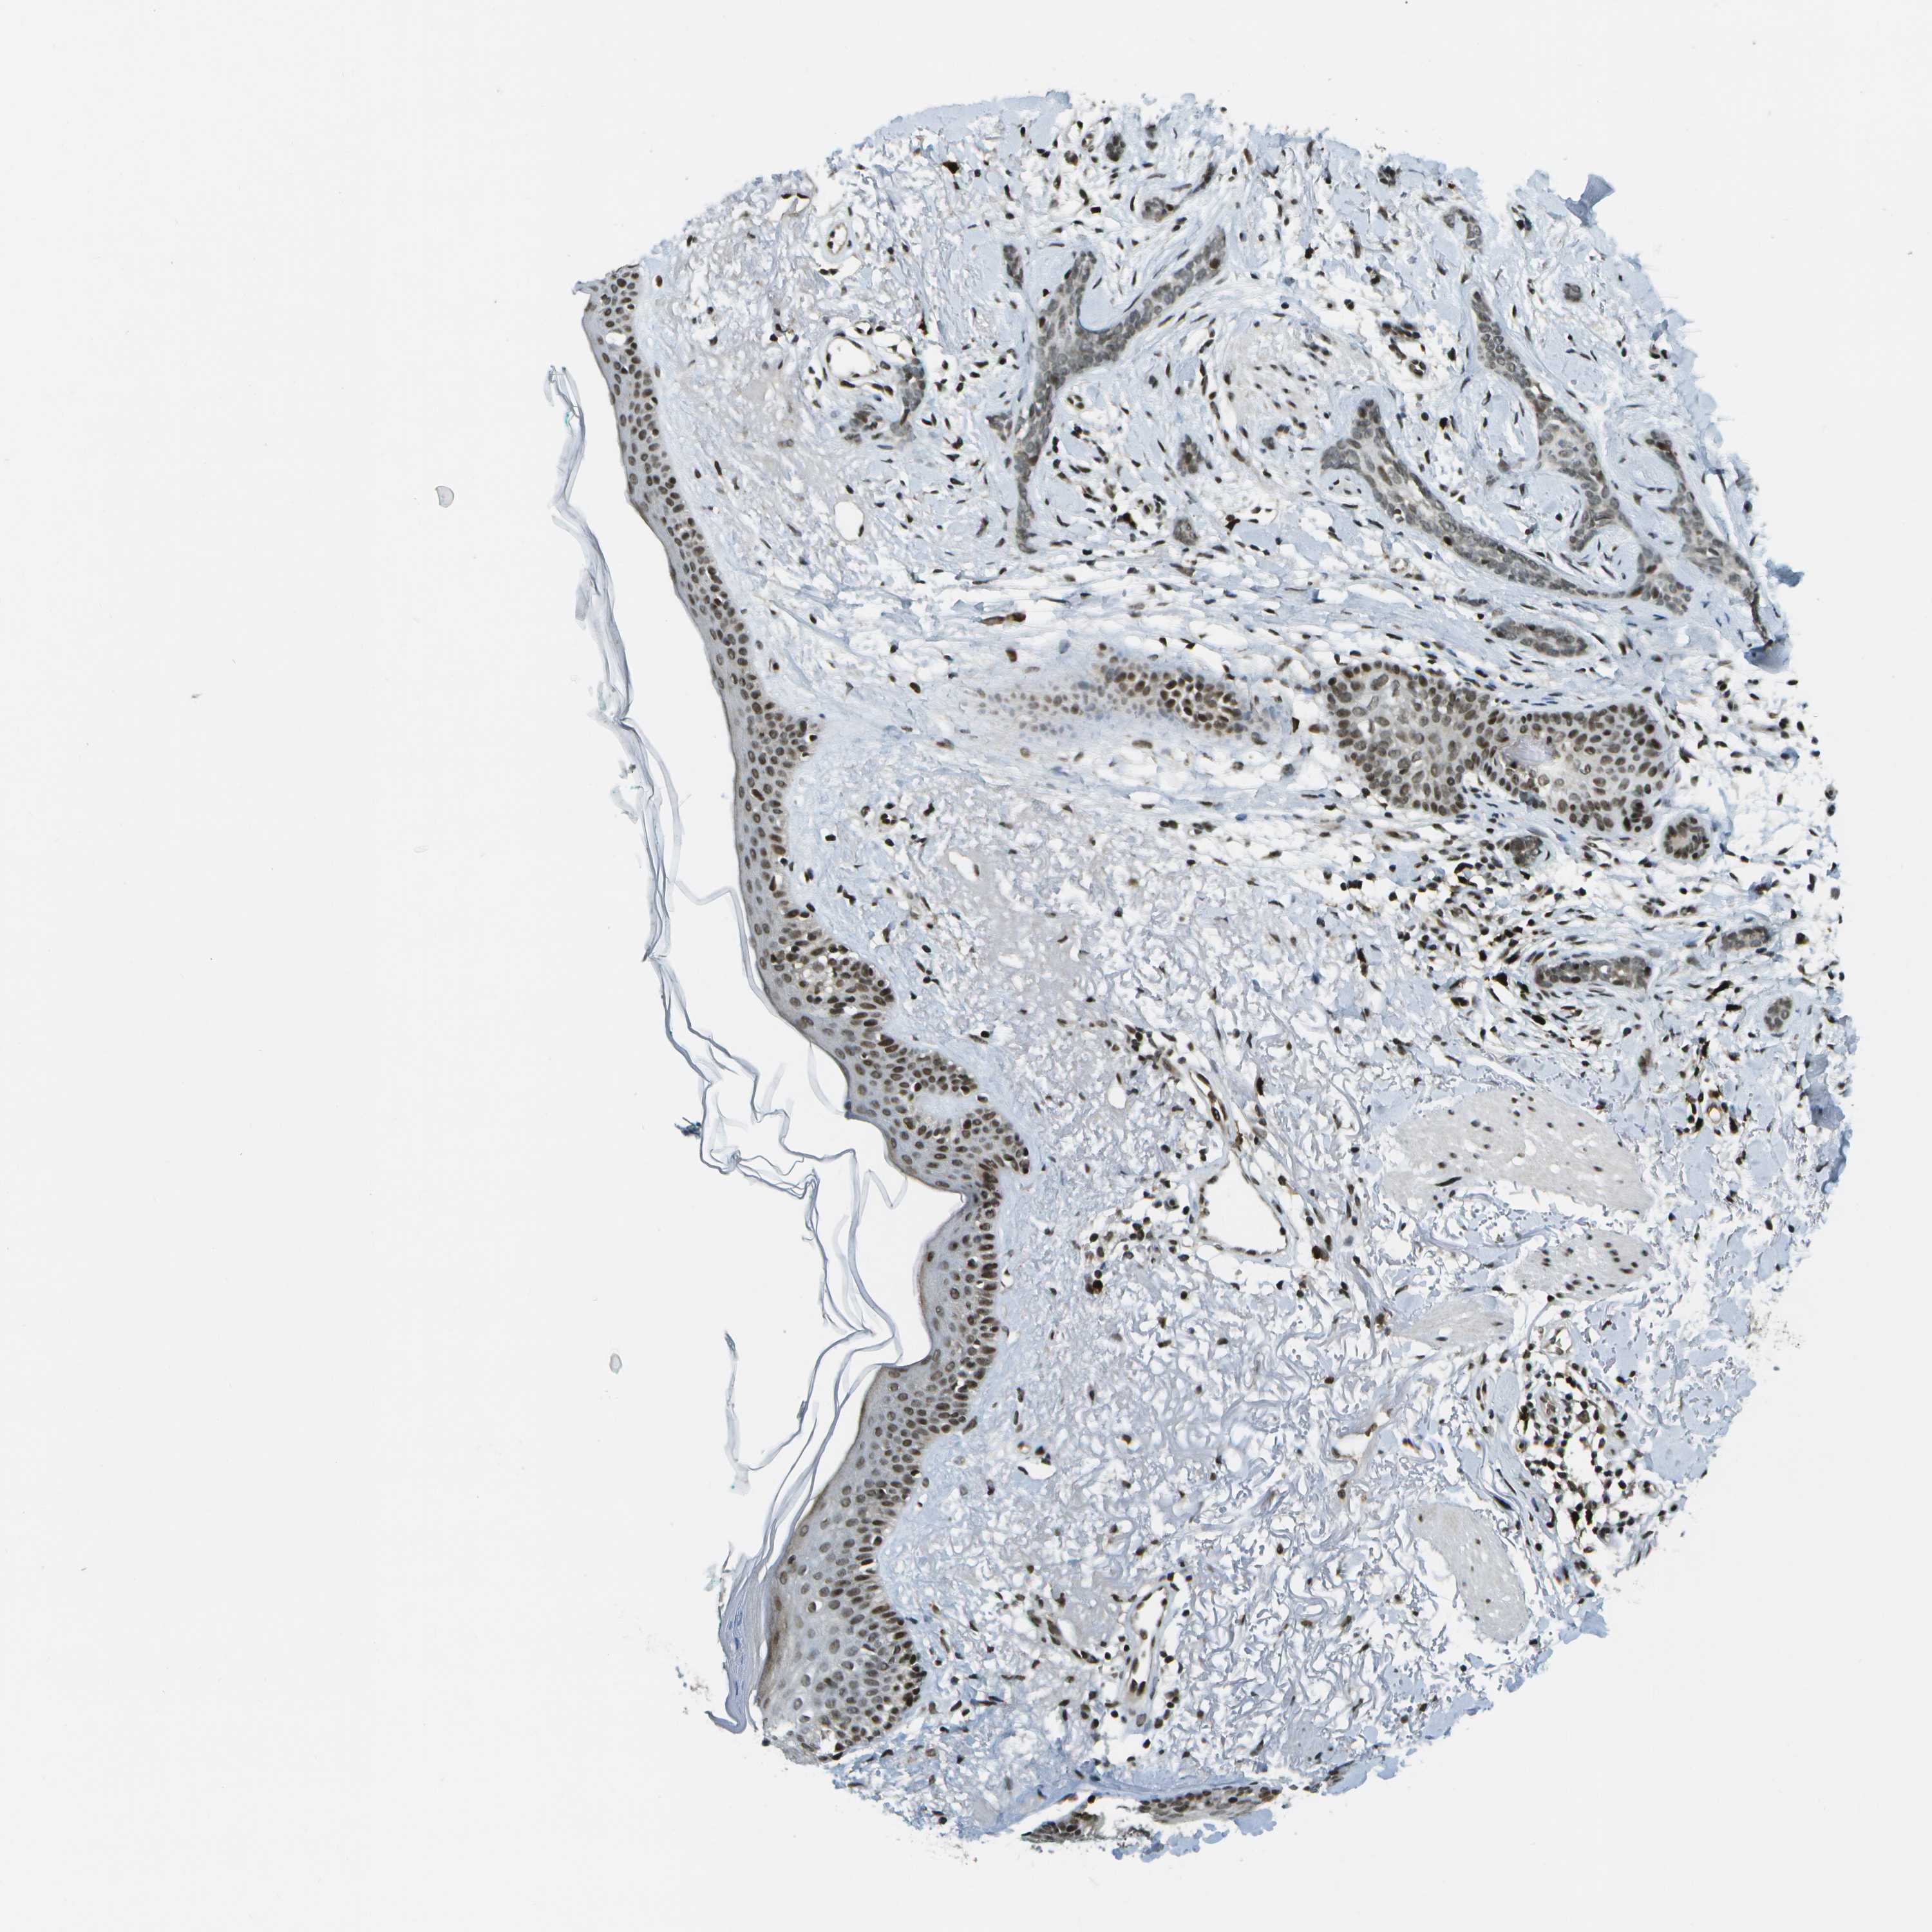

SKIN CANCER - Protein expressioni

A mouse-over function shows sample information and annotation data. Click on an image to view it in a full screen mode. Samples can be filtered based on level of antibody staining by selecting one or several of the following categories: high, medium, low and not detected. The assay and annotation is described here.

Antibody stainingi

Antibody staining in the annotated cell types in the current human tissue is reported as not detected, low, medium, or high, based on conventional immunohistochemistry profiling in selected tissues. This score is based on the combination of the staining intensity and fraction of stained cells.

Each image is clickable and will lead to virtual microscopy that enables deeper exploration of all samples and also displays staining intensity scores, fraction scores and subcellular localization as well as patient and tissue information for each sample.

Antibody CAB017694

Squamous cell carcinoma, NOS

Adnexal tumor, benign